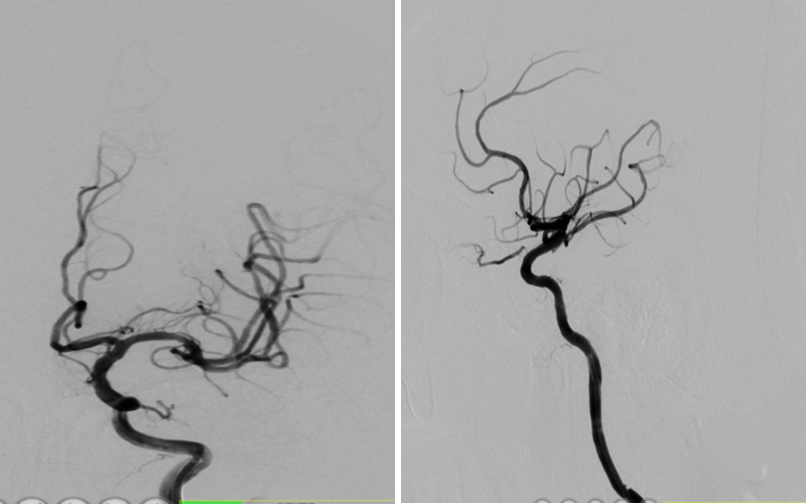

导丝怎么扩【载药时代 球扩天下】NOVA DES®颅内药物洗脱支架在颈内动脉颅内段重度狭窄中的应用体会二例!_https://www.jmylbn.com_新闻资讯_第20张

导丝怎么扩【载药时代 球扩天下】NOVA DES®颅内药物洗脱支架在颈内动脉颅内段重度狭窄中的应用体会二例!_https://www.jmylbn.com_新闻资讯_第21张

重要影像结论:右侧颈内动脉C4段重度狭窄;右侧颈内动脉C6段中度狭窄;左侧颈内动脉C5段中度狭窄;左侧大脑前动脉A1段重度狭窄。